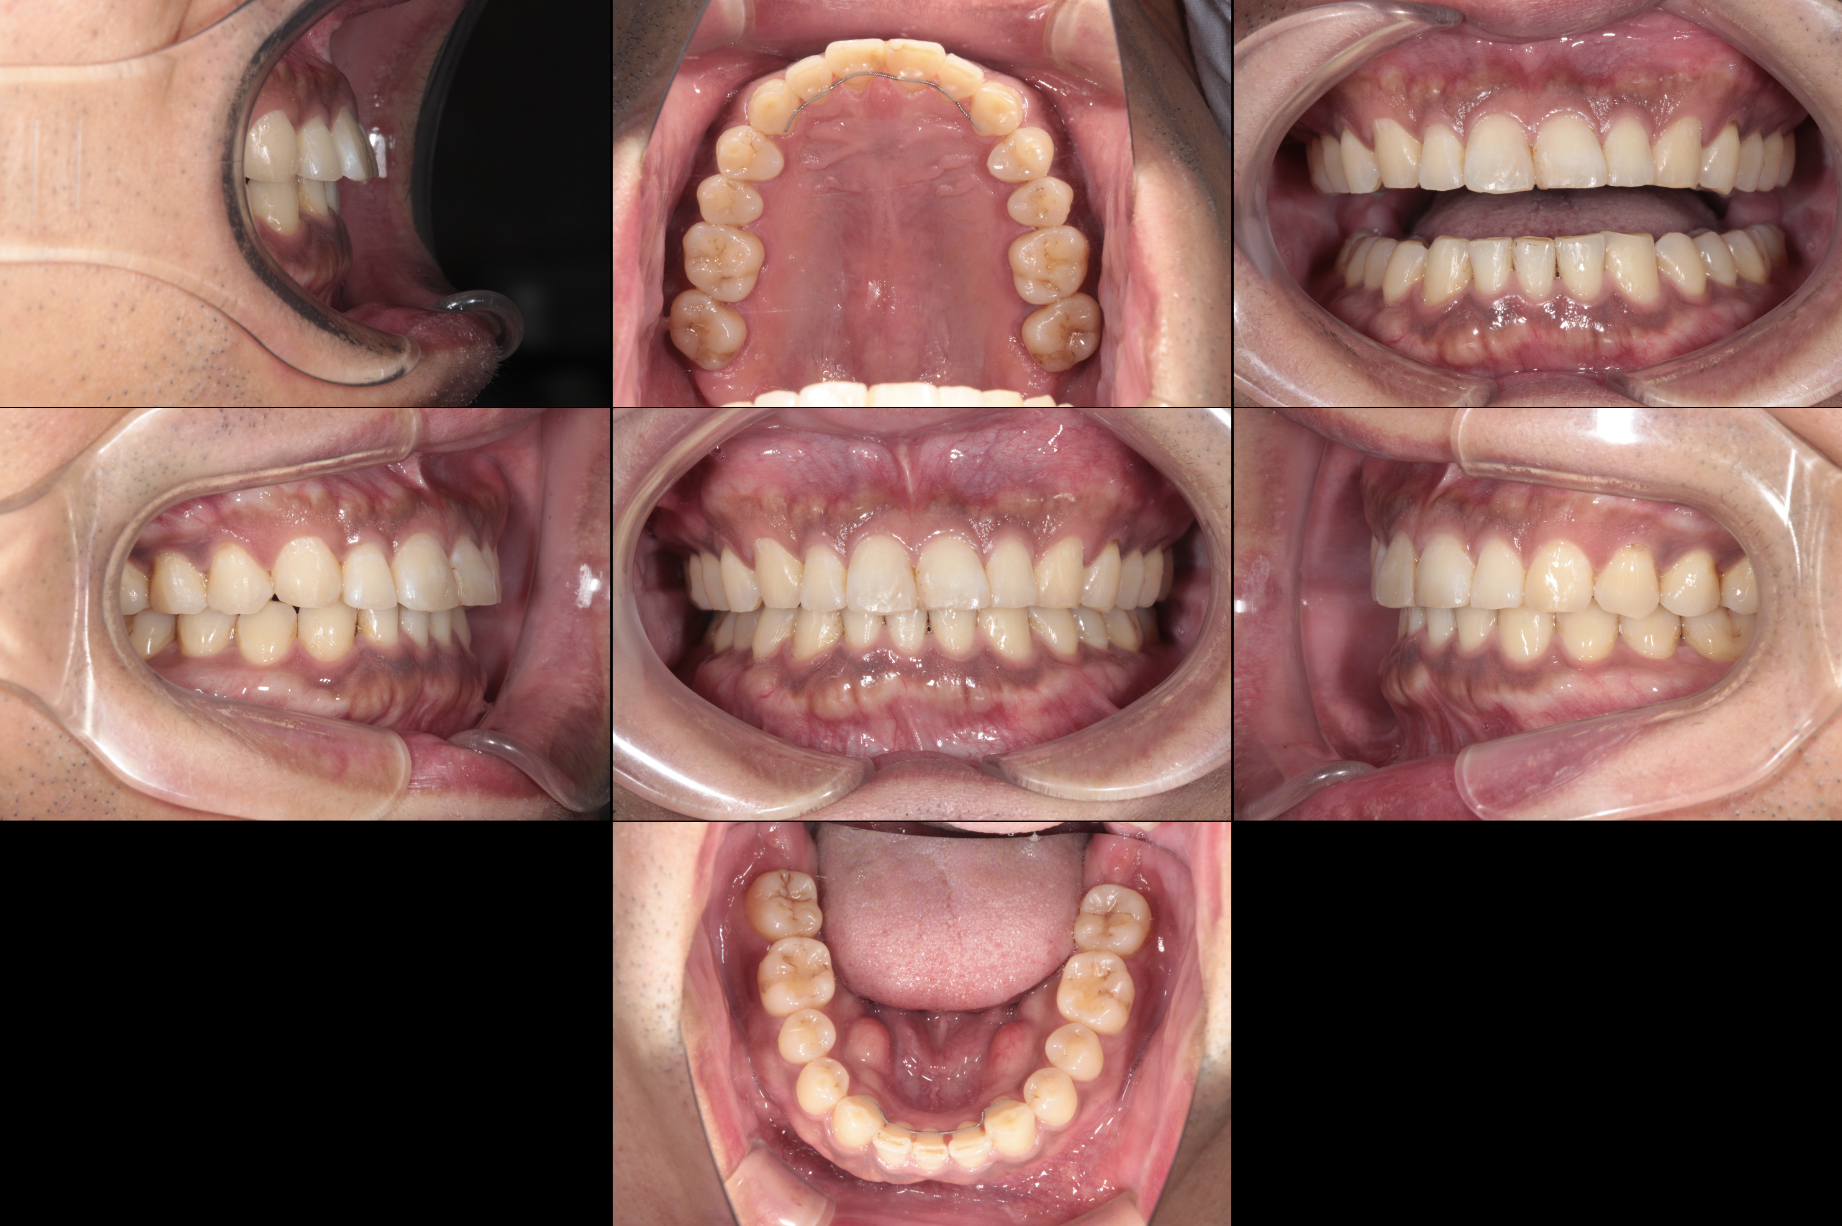

初診時、口腔内を確認すると、下顎前歯部に明らかな叢生を認めました。

治療は、右下2番の抜歯からスタートしました。

まず、抜歯スペースを活用して前歯のガタつきを徐々に整え、咬合平面が水平になるようコントロールしました。

口元の印象も自然になり、下唇の張り感が和らぎ、横顔のバランスが改善。

患者さん自身も、「前歯の裏が驚くほど磨きやすくなった」「歯ぐきが健康になった気がする」と笑顔で話してくださいました。